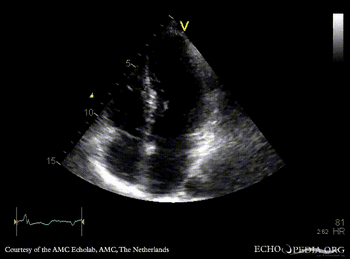

E00504.gif E00505.gif

A4CH: concentric hypertrophy of left ventricle, SAM of AMVL A3CH